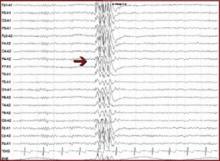

EEGs: EPILEPTIFORM ACTIVITY INDICATES POTENTIAL FOR SEIZURES

On an EEG, epileptiform activity is seen as spikes or sharp waves and indicates potential for epileptic seizures.

• Focal epileptiform activity is consistent with seizures of focal origin (e.g., simple partial, complex partial, or partial onset seizure with secondary generalization into tonic-clonic seizure).

• Generalized epileptiform activity is consistent with seizures of generalized onset (e.g., absence, myoclonic, or primary generalized tonic-clonic seizure).

Interictal spikes (between seizures) are consistent with, but not diagnostic of, seizures and epilepsy. An ictal discharge (rhythmic, persistent epileptiform activity) on an EEG accompanied by a clinical change in behavior is diagnostic of a seizure.

Focal epileptiform activity

Generalized epileptiform activity

This patient presents with symptoms that could be consistent with absence seizures. EEG would be diagnostic if it showed generalized spike and wave. Absence seizures (sometimes called petit mal) usually present in childhood and are characterized by recurrent brief staring spells with no postictal confusion or other clinical manifestations.

EEG shows characteristic generalized three-per-second spike and wave, which is often precipitated by hyperventilation or photic stimulation. Ethosuximide or valproate can completely control seizures in most cases.